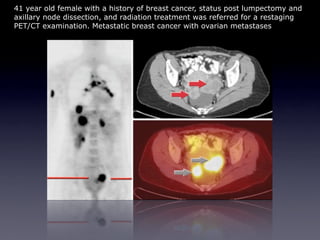

The sculpture "The Short, Rich Life of Positronium" commemorates fundamental research on antimatter conducted at the University of Michigan. Positron emission tomography (PET) uses positron-emitting radioactive isotopes as tracers and coincidence detection of the resulting back-to-back photons to construct tomographic images. PET enables visualization of functional processes in the body by tracking radioactive tracers like fluorodeoxyglucose, which is used to show glucose metabolism and thus tissue activity. While providing valuable medical information, PET also involves some radiation risks due to the penetrating nature of the emitted photons.